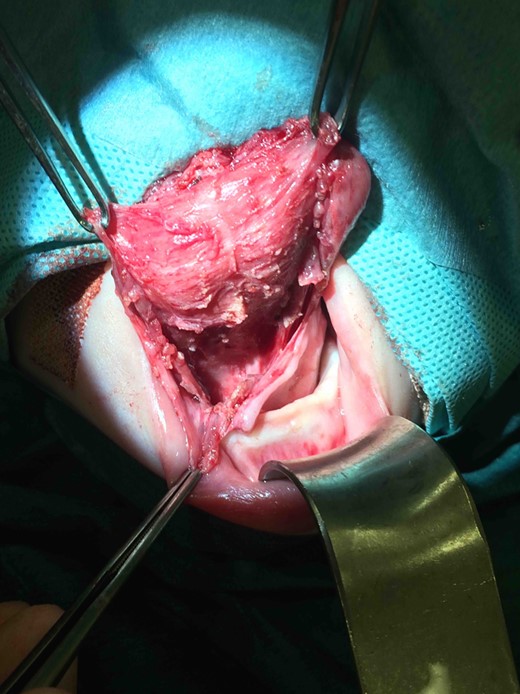

Clinic follow-up was expedited at age 5 weeks, as the cyst had increased rapidly in the preceding 10 days, resulting in impaired feeding. On examination, there was considerable swelling of the anterior tongue and floor of mouth, and the tongue was pushed superiorly against the hard palate and anteriorly, protruding past the lips. Interestingly there was no airway compromise. Fifteen millilitres of grey-brown fluid were aspirated from the cyst, which provided immediate reduction in swelling and improvement in feeding. It was planned to review the baby in 3 weeks with a view to future surgical excision, but to await microscopy and culture of the fluid and allow the neonate to grow further. Culture of the fluid showed no bacterial growth. However, at follow-up the cyst had re-collected to fill the entire oral cavity. Again there were no signs of airway compromise. Twenty millilitres of fluid were aspirated and the patient was booked for urgent surgical excision of the cyst. A horizontal sublingual incision above the submandibular duct openings was performed. The submandibular ducts and lingual nerves were identified and preserved. A cyst measuring 48 mm × 20 mm × 5 mm was excised, which extended up to the foramen caecum posteriorly (Figs 2–4). The defect was closed with vicryl rapide 4/0, and a small opening was left anteriorly and posteriorly to facillitate drainage. Histology showed that the cyst wall was lined by stratified squamous epithelium in some areas and bundles of smooth muscle in others. Additionally, there were small cystic structures lined by mucin-producing columnar cells. These appearances were consistent with the clinical diagnosis of a cystic thyroglossal duct remnant.

Intraoperative photograph demonstrating surgical excision of the thryoglossal duct cyst.